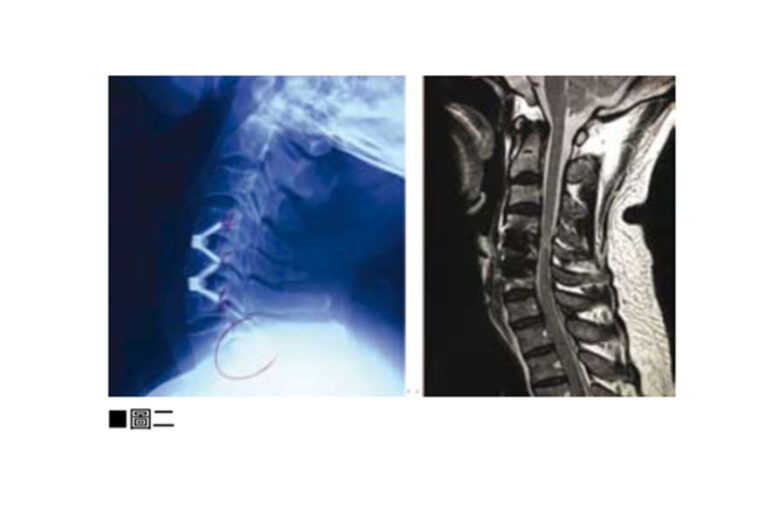

頸椎前路椎間盤切除及椎體融合手術(Anterior Cervical Discectomy and Fusion,ACDF)是以外科手術來治療頸椎的病變問題。導致頸椎病變多是因退化性、勞損性或意外受傷造成。病變會發生在頸椎間盤、頸椎的小面關節,或是頸椎體骨。由於頸椎中央包含了負責控制我們四肢、軀幹及大小便的中樞神經,所以頸椎病人除了有頸椎不穩定的症狀外,亦會有神經受壓的病徵。頸椎不穩定會引起肌肉繃緊、頸背痛、膊頭痛及頭痛。而神經受壓會令感官神經及運動神經功能失調,病人會有手腳神經麻木痺痛、肌肉無力、平衡失調、行路不穩、小便頻密、夜尿及便秘情況。此外反射神經及交感迷走神經的功能失調,亦會導致病人頭暈、耳鳴、腸胃不適甚至情緒不穩定。